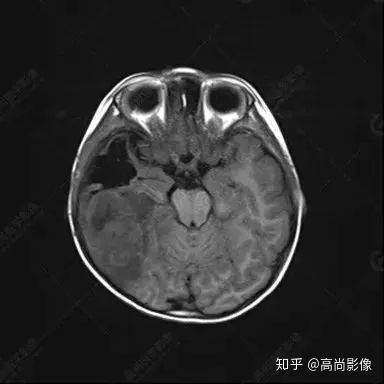

右側(cè)顳葉腫瘤切除術(shù)后(具體不詳):右側(cè)顳部骨質(zhì)不連續(xù)呈術(shù)后改變,右側(cè)顳葉術(shù)區(qū)見片狀長T1長T2信號影,F(xiàn)LAIR呈低信號;術(shù)區(qū)后方右側(cè)顳枕葉見一巨大占位性病變影,邊界欠清,大小約6.2×5.8×4.3cm(前后×左右×上下),信號不均勻,T1WI呈等稍低信號間雜少許高信號,T2WI呈高稍低混雜信號,DWI示部分病灶彌散受限,相應(yīng)ADC圖減低,磁敏感序列見部分呈極低信號,增強(qiáng)掃描可見明顯不均勻強(qiáng)化,鄰近硬腦膜及小腦幕增厚并明顯強(qiáng)化;另延髓右前方及右側(cè)橋小腦角區(qū)見一不規(guī)則形異常信號影,大小約3.2×1.3×3.7cm(左右×前后×上下),呈長T1稍長T2信號,F(xiàn)LAIR呈等信號,DWI未見受限,增強(qiáng)后明顯均勻強(qiáng)化,鄰近腦膜明顯強(qiáng)化。鄰近腦實質(zhì)及右側(cè)顳角明顯受壓;左側(cè)大腦半球未見局灶性信號異常,中線結(jié)構(gòu)稍左移。

右側(cè)顳葉腫瘤切除術(shù)后:現(xiàn)術(shù)區(qū)后方右側(cè)顳枕葉及延髓右前方占位,右側(cè)顳枕部硬腦膜及小腦幕明顯強(qiáng)化,結(jié)合既往影像資料,考慮為胚胎源性惡性腫瘤,如非典型畸胎樣/橫紋肌樣瘤(AT/RT)或原始神經(jīng)外胚層腫瘤(PNET)。

術(shù)后隨訪病理結(jié)果:非典型畸胎樣/橫紋肌樣瘤。